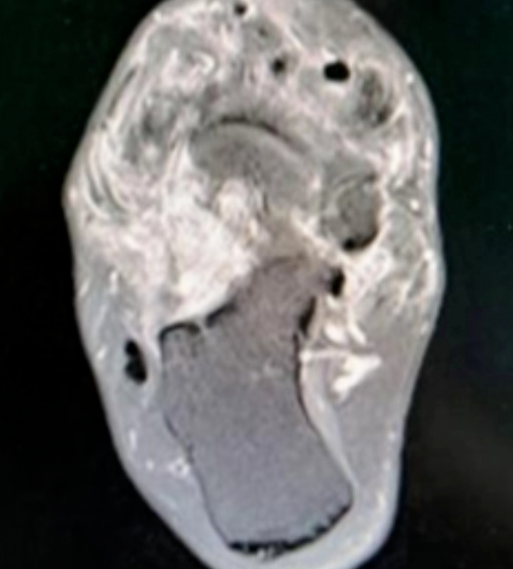

丽姐(化名)患足部腱鞘巨细胞瘤多年,已进行多次手术却又复发,并且肿瘤侵犯关节、累及关节面,严重影响了她的生活质量。

丽姐来到中国医学科学院肿瘤医院深圳医院骨科就诊时,肿瘤范围分布广泛,后确诊弥漫型腱鞘巨细胞瘤。